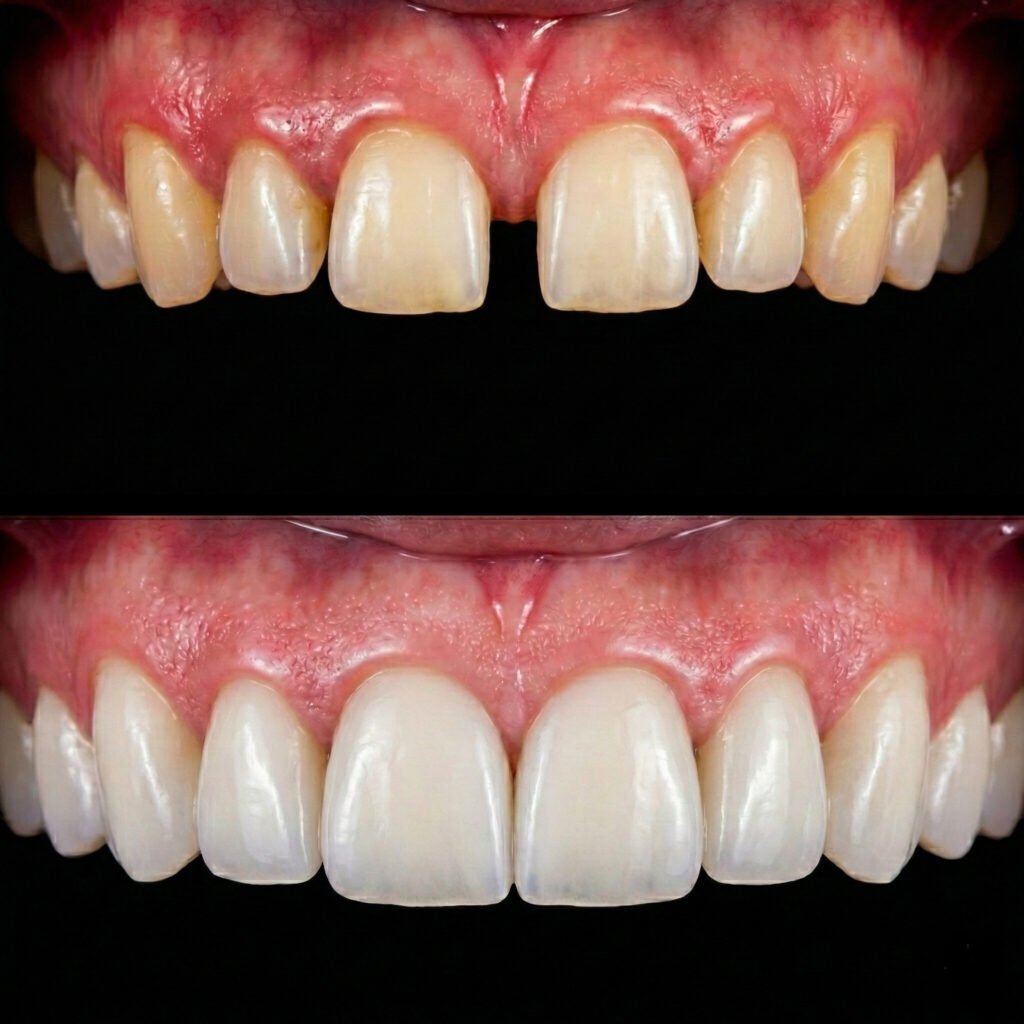

hollywood smile agadir

Hollywood Smile

Un relooking Hollywood Smile sur mesure pour un sourire lumineux, harmonieux et sophistiqué.

facettes dentaires agadir

Facettes Dentaires

Transformez votre sourire en toute confiance avec des facettes dentaires adaptées à vos besoins.